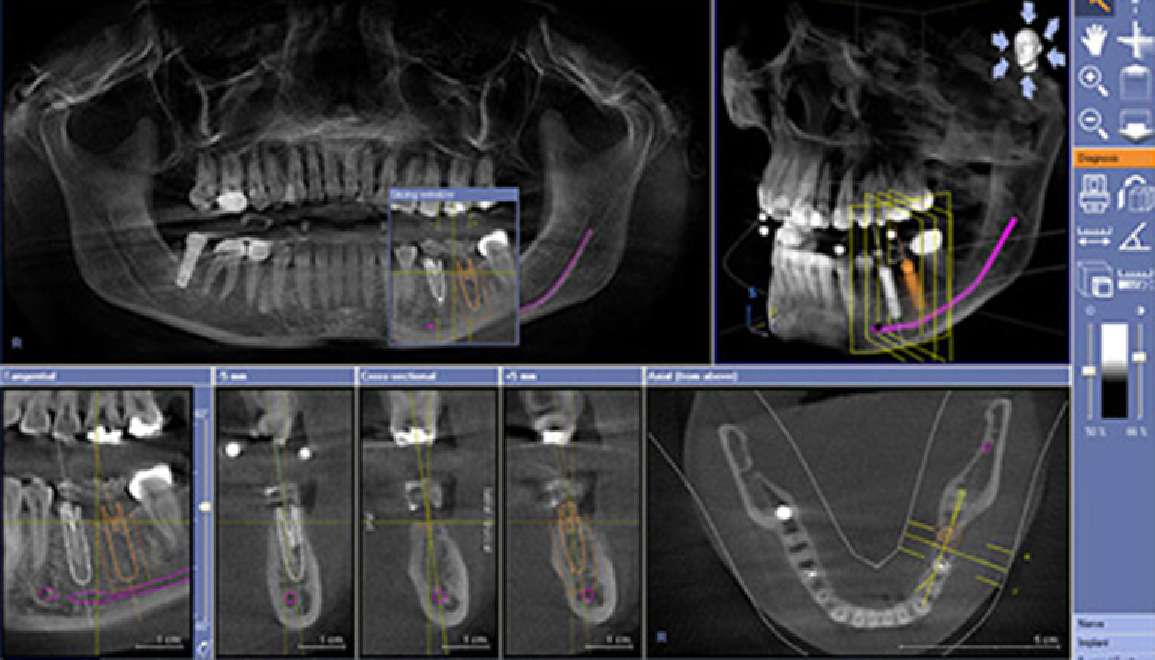

●3Dシミュレーション

CTで撮影した画像を元に、インプラントを骨にどの角度でどの位の深さで埋入するかを3次元でシミュレーションします。